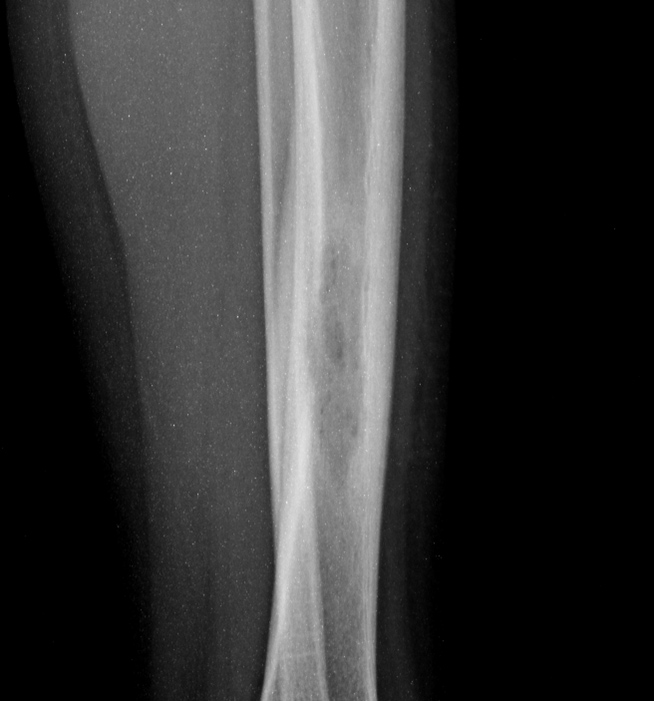

男孩,5岁,左小腿疼痛,肿胀,活动受限20天。

左胫骨中下段见一长卵圆形骨质破坏区,走形方向与胫骨长轴一致,边缘轻度硬化,内后侧骨皮质破坏,伴明显骨膜增生,破坏区内呈软组织密度。未见明显软组织肿块。

意见:左胫骨嗜酸性肉芽肿可能性大。

鉴别:本病主要与胫骨恶性肿瘤,尤其尤文氏瘤鉴别。后者骨质破坏范围更广、破坏区边缘往往不规则,骨膜增生更明显、骨膜增生可见较明显的骨质破坏,放射状骨针常见,多见软组织肿块。一般可以鉴别,当然确诊有赖于病理学检查。另外,与骨髓炎等鉴别不难。

左胫骨中下段见一不规则虫蚀样骨破坏,走形方向与胫骨长轴一致,边缘轻度硬化,伴明显骨膜增生,ct见破坏区内见磨玻璃样密度,其旁软组织钟胀,内见不规则钙化。

考虑:骨纤垩变可能性大,嗜酸性肉芽肿亦不除外.

左胫骨中下段见一不规则虫蚀样骨破坏,走形方向与胫骨长轴一致,边缘轻度硬化,伴明显规则的骨膜增生,ct见破坏区内见磨玻璃样密度,其旁软组织钟胀,内见不规则钙化。

考虑:嗜酸性肉芽肿。骨髓炎与尤文氏瘤待排

病史资料不完善,根据年龄、部位、及影像学表现,主要表现胫骨骨干囊性骨质破坏,骨皮质受累,局部骨膜反应,未见骨膜破坏及瘤骨,未见放射状骨针。 首先要考虑胫骨转移瘤,建议进一步检查,除外视网膜母细胞瘤,神经母细胞瘤,肾母细胞瘤,肾上腺等恶性肿瘤骨转移。排除转移瘤后考虑嗜酸性肉芽肿可能性大,患者年龄5岁,尤文氏瘤不太考虑,骨肉瘤也不太符合,骨髓炎待排,影像表现不太支持。建议进一步检查,除外原发恶性肿瘤胫骨转移后,考虑嗜酸性肉芽肿。必要时穿刺活检。